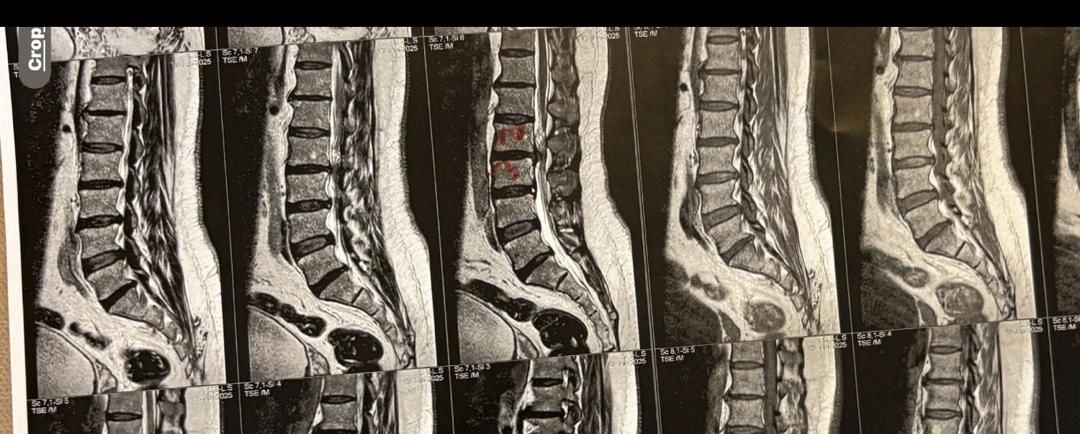

32 years female patient presented to my office one year ago with moderate cervical pain and R. Arm pain ,mild LBP with no radicular pain. Her mri in C/s had few bulges and few segmentsl dysfunctions

Her lumbar mri showed Contained R. Para. L5-S1 extrusion

She got treatment just for her neck and exercises for her low back. Few months later had lumbar disc surgery

Few days ago on may on june 08/2025, presented with severe LBP and no radicular pain

I have post her lumbar MRI before and after surgery. I consulted with a neurosurgeon at our clinic and he said doesn’t need another surgery because doesn’t have radicular pain or neurological deficits

For her pain i have started to do mild decompression by Cox and DTS and acupuncture, no adjustment whatsoever.

Please mention what differences you see before and after surgery